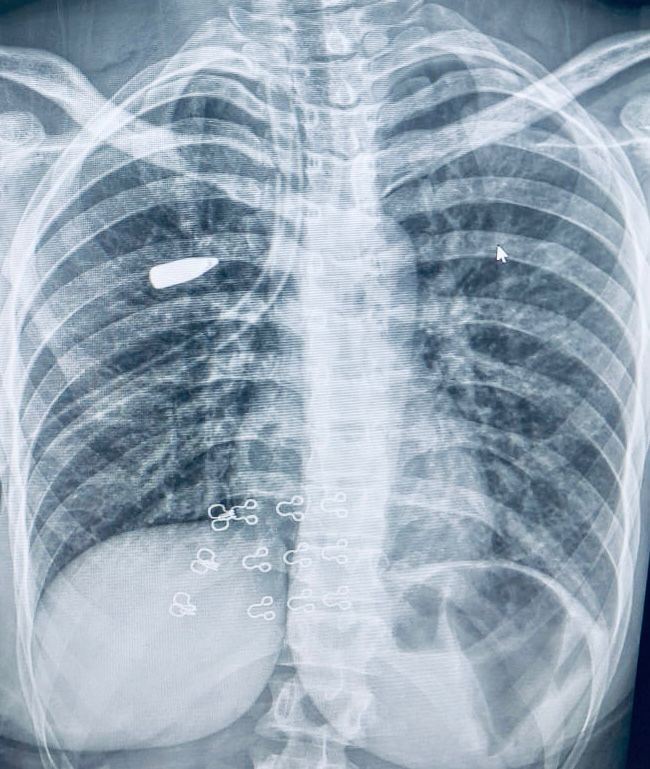

وعلى الفور، قام الفريق الطبي بإجراء الفحوصات والإجراءات اللازمة، والتي كشفت عن استقرار المقذوف الناري داخل أنسجة الرئة اليمنى.

وتم مناظرة دقيقة للحالة وإجراء الأشعات اللازمة التي أكدت استقرار المقذوف بين أغشية الرئة، ليقوم الفريق الطبي بإجراء جراحة دقيقة للغاية، وتم استخراج المقذوف الناري بنجاح باستخدام منظار الصدر الجراحي من خلال فتحة جراحية لا تتعدى 2 سم، مما ساهم في الحفاظ على سلامة الرئة وتقليل التلف إلى أدنى حد، بالإضافة إلى الحفاظ على الشكل الجمالي لجدار الصدر.